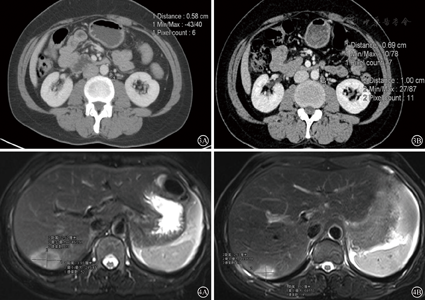

患者44岁女性,以"体检发现乙状结肠肿块3月"为主诉入院,查体未见明显异常。肠镜示:距肛20 cm结肠新生肿物,结肠多发息肉,病检:腺癌。腹部增强CT提示:乙状结肠肠壁增厚,浆膜面毛糙,动脉期强化明显,局部见多发肿大淋巴结,腹中动脉可见一枚短径5.8 mm淋巴结(见图3A)显示,肝右后叶肿块影。胸部平扫CT未见异常。上腹部增强MRI提示肝右后上段见大小约3.9 cm×2.5 cm肿块影(见图4A),动脉期不均匀明显强化。AFP:1.51 ng/ml(正常<8 ng/ml),CEA:84.77 ng/ml(正常<3.4 ng/ml)。初步诊断:乙状结肠癌伴肝、腹主动脉旁淋巴结转移(cT4aN2M1b,IV期)

经过3周期mFOLFOX6方案化疗后,患者乙状结肠肿瘤未见明显缩小,腹主动脉旁淋巴结(para-aortic lymph node,PALN)增大(见图3B),肝转移灶缩小至2.6 cm×1.9 cm(见图4B),遂行乙状结肠癌根治术、腹主动脉旁淋巴结清扫、右肝肿瘤局部切除术。